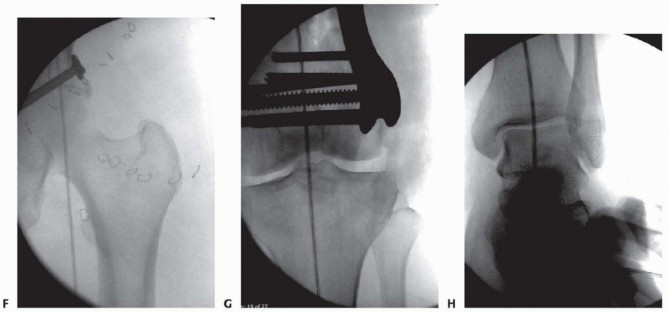

### TECH FIG 5 • A. Distal reference pin is placed to ensure that the proximal pin is parallel to the joint. B. Clinical picture depicting the guide. C. Different patient showing the penetration of the medial side with the guidewires to allow plate placement. D,E. The plate is placed with additional guide pins in place. - F,G. Lateral intraoperative fluoroscopic images ensure proper plate placement on the femur before screw insertion. To solve this, the guidewires can be driven through the medial side of the knee, which is distal enough to be safe ( TECH FIG 5C). The plate can then be inserted submuscularly and the guidewires driven back through the plate laterally, thus aligning the plate to the distal segment and ensuring proper screw trajectory and plate placement ( TECH FIG 5D,E). A single guidewire in a central hole will still allow flexion-extension placement of the plate if this needs to be adjusted. After placing the initial guidewire parallel to the joint distally, and ensuring the fracture is reduced, the surgeon should obtain fluoroscopic visualization of the plate proximally on the shaft to ensure that the plate is on the bone ( TECH FIG 5F,G). To ensure placement of the plate on the bone both proximally and distally, it is best to stabilize the plate distally 483 (where exposure is) using a guidewire in the center hole. This allows for a pivot point around which the AP positioning of the plate can be manipulated for the shaft. Fluoroscopy to image the lateral is then used to ensure placement.

--- TECH FIG 6 • A,B. Patient seen in FIG 15C,D, with the guidewire now pulled back and an appropriately sized screw placed. Once the AP position is obtained, the plate is stabilized proximally. The plate should be temporarily stabilized to the bone proximally. Before the temporary stabilization, the length and rotation must be checked. Ideally, if the temporary fixator is in place, these two parameters have been maintained during the course of the operation. If no screw targeting guide is present, a percutaneous provisional fixation pin can be used to stabilize the plate. If a targeting guide is used, then a soft tissue guide for the most proximal hole is placed percutaneously and a drill bit or guidewire is used to stabilize the plate. The variable-angle locking plates also have proximal shaft targeting devices; however, variable locking trajectories can only be accomplished outside the targeting device and can be cumbersome. Generally, variable-angle locking is not necessary in the shaft and locking screws collinear with the hole can be placed through the targeting device. ( FIG 11E, red arrows showing perpendicular nature of locking screws; FIG 11F, variable-angle locking screws in the shaft are useful in cases where there is a preexisting hip replacement with a femoral component.) Again, the flexion-extension reduction should be checked. This procedure creates our “box” construct, which aids in the placement of screws through the targeting device (if used) and in temporary stabilization of the fracture construct. ### Screw Placement If the intercondylar split is going to be stabilized by screws through the plate, partially threaded screws or overdrilled fully threaded screws should be used first to provide interfragmentary compression. Specially designed conical screws for certain systems exist, or large partially threaded screws can be used ( >4.5 mm). This also compresses the plate to the bone. Once the articular injury is addressed, at least two additional locking screws should be placed into the distal segment to secure the plate and the alignment. The trajectory of distal locking screws can be assessed on the notch view to ensure that penetration through the intercondylar notch does not occur ( TECH FIG 6; see FIG 15C for C-arm setup and position for this image). Before placing the locking screws, the length, rotation, and alignment must be checked again if no fixator or distractor is in place holding the fracture alignment. The plate can be locked to the distal segment and then used to manipulate the distal segment relative to the shaft for the flexion-extension reduction. This, however, is predicated on proper distal alignment of the plate. Otherwise, once the plate is fixed to the distal segment in a malposition and the fracture reduced, the plate may be anterior or posterior on the shaft. The distal screws in a variable-angle locking plate are noncircular to allow for the variable-angle locking mechanism. Screws can be placed directly collinear or with a “variability” of 15 degrees in any direction depending on the system used (see FIG 11D, square outline). ### Attaching the Distal Segment to the Shaft The distal segment is now fixed and can be attached to the shaft. If there is malalignment in the coronal plane but the sagittal plane alignment is reduced, the shaft can be “pulled” to the plate by means of various threaded devices or a nonlocking screw that can be placed freehand under fluoroscopic guidance or through a targeting jig ( TECH FIG 7). ### Placement of Additional Screws Once proper reduction of the fracture is temporarily achieved and the plate is in proper position, additional screws can be placed. If the targeting screw guide is used, percutaneous locking screws can be placed through the soft tissue drill or screw guides ( TECH FIG 8A-C). If no targeting guide is available, fluoroscopic guidance and a percutaneous method can be used freehand. 484